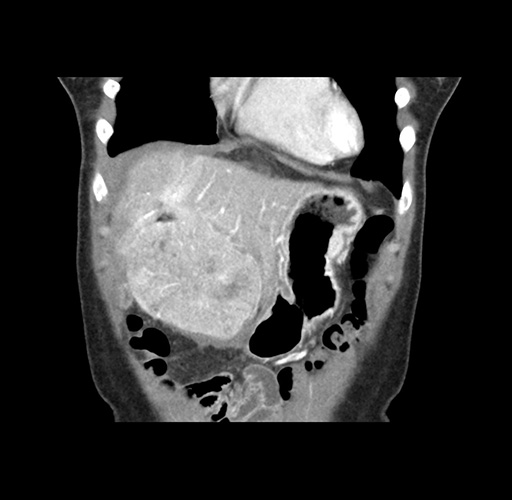

Imaging Analysis

Look through the patient's CT scan to identify any areas of concern for the necessary procedure.

Based on your CT findings, which issue(s) would give reason for "planned slowing down moment(s)" in this case?